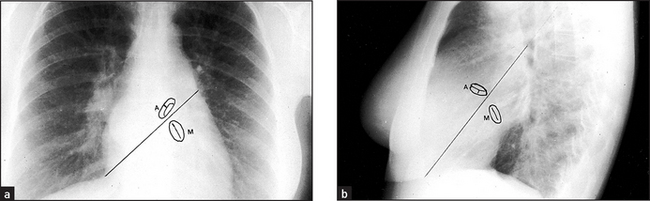

Figure 8.2 Normal chest X-ray (a) The posteroanterior view shows: (1) aortic knuckle; (2) left heart border formed by the lateral border of the left ventricle; (3) left hilum, formed mostly by the left main pulmonary artery and partly by the left upper pulmonary veins; (4) right heart border formed by the right atrium; (5) inferior angle of the scapula; (6) right basal pulmonary artery; (7) medial aspect of the left clavicle; (8) spine of the scapula; (9) right cardiophrenic angle; and (10) superimposition of the right lateral margins of the superior vena cava and the ascending aorta. (b) The lateral view shows: (11) anterior border of the trachea; (12) pulmonary vein, entering the left atrium; (13) oblique fissure; (14) left hemidiaphragm; and (15) right hemidiaphragm.

Mitral valve calcification is seen below an imaginary line drawn from the anterior costophrenic angle to the hilum, whereas aortic valve calcification lies above this line.

Figure 8.6 Mitral valve disease The left atrium enlarges because of the pressure and volume load. It bulges posteriorly and to both sides (arrows). The atrial appendage bulges out below the left hilum. The prominent right border of the atrium causes the ‘double right heart border’ appearance. To distinguish the valves if calcification is present, draw imaginary lines. On the PA view (a) the line passes from the right cardiophrenic angle to the inferior aspect of the left hilum. The line on the lateral view (b) passes from the antero-inferior angle through the midpoint of the hilum. The aortic valve lies above this line whereas the mitral valve lies below it.